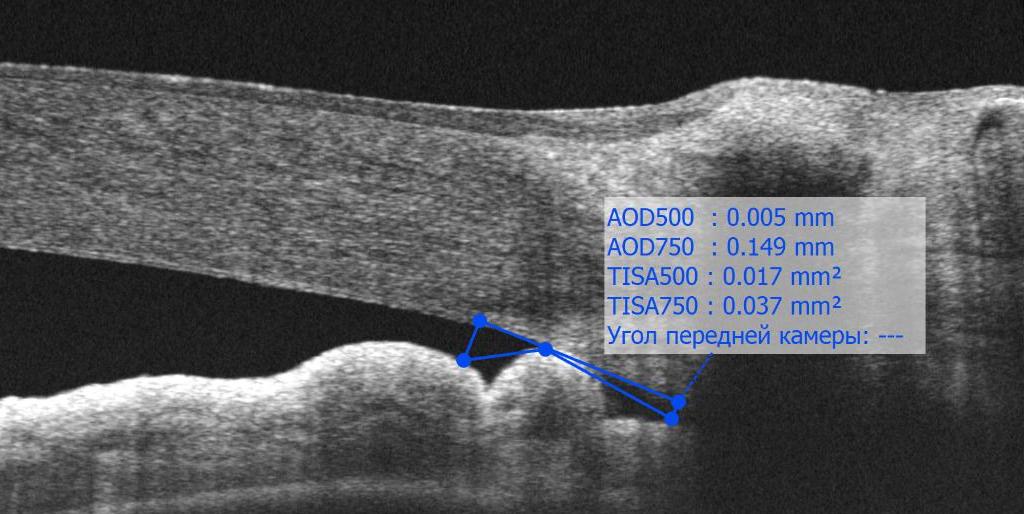

МАТЕРИАЛ И МЕТОДЫ. Проспективное исследование включало 120 пациентов от 41 до 80 лет (60 глаз – ПЗУ, 30 – ППЗУ, 30 глаз – без офтальмопатологии). Исследуемые параметры включали: сфероэквивалент (СЭ), внутриглазное давление (ВГД), толщину хориоидеи в фовеоле (ТХф), аксиальную длину (AL), глубину передней камеры (ACD), высоту свода хрусталика (LV), кривизну радужки и ее толщину, профиль угла передней камеры (УПК): AOD500, AOD750, TISA500, TISA750.

РЕЗУЛЬТАТЫ. ППЗУ отличалась от контроля увеличенными СЭ, LV, ВГД, кривизной радужки, ТХф, уменьшенными ACD, AL, и профилем УПК (AOD500, AOD750, TISA500, TISA750) в вертикальных секторах (все p<0,01), по толщине радужки группы были сопоставимы. ПЗУ отличалась от ППЗУ увеличенными СЭ, LV, ВГД, уменьшенными ACD, AL, AOD500 в верхнем секторе и профилем УПК в нижнем секторе (все p<0,01). Толщина радужки и ее кривизна, а также профиль УПК в верхнем секторе и ТХф были сопоставимы. Определены пороговые значения, отличающие ППЗУ и ПЗУ: LV – 0,656 мм, AOD500 – 0,131 мм, TISA500 – 0,051 мм2, TISA750 – 0,093 мм2 в нижнем секторе, ВГД 21 мм рт.ст. В многофакторной модели с поправками на возраст, пол и AL установлена обратная взаимосвязь толщины радужки с ТХф как при ППЗУ, так и при ПЗУ (все p<0,01), но не в контроле (все p>0,01).